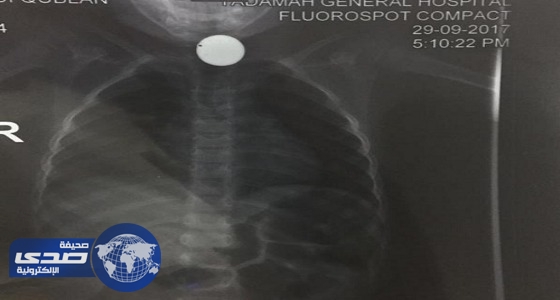

فريق طبي ينقذ حياة طفل ابتلع قطعة معدنية في نجران

منذ 7 سنة

1

3309